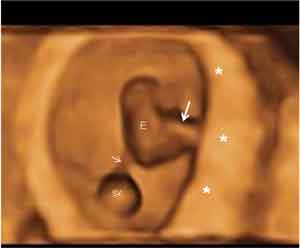

Ecografía en 3D de embarazo de 7,5 semanas

Saco vitelino, placenta y cordón en un embarazo de 7,5 semanas (ecografía 3D). En un lado vemos el cordón umbilical (flecha larga) entre el embrión (E) y la placenta (*) y en el otro extremo el saco vitelino (sv) con el tallo de unión (flecha corta) al embrión.